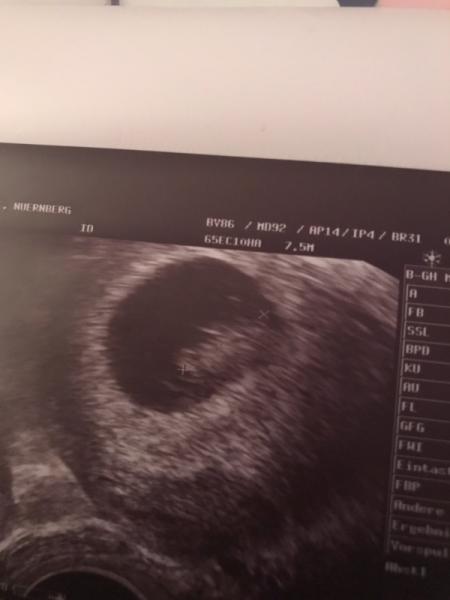

Wir hatten heute nochmal einen fa Termin, und unserem kleinen Gummibärchen geht es prima, das Herzchen schlägt fleißig, die ganz stolze Tante war heute mit bei der Untersuchung und konnte ihre Tränen nicht zurückhalten. Es ist so unglaublich süß gewesen

Bild zu Überglücklich &‘ alles gut - Forum für Juli - Mamis